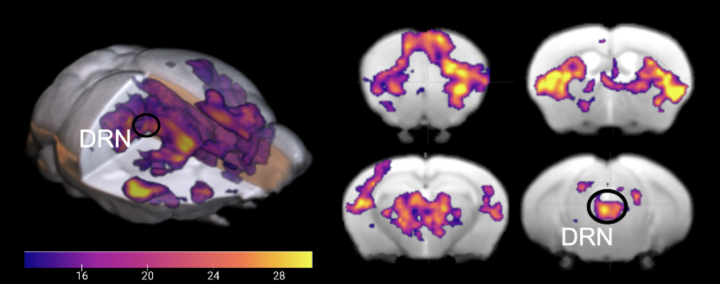

Activation of the brain when the DRN is stimulated in awake states

In awake states, when serotonin neurons in the dorsal raphe nucleus (DRN) are stimulated by light, specific areas of the brain are activated at different levels of intensity. Credit: Hamada et al., 2024